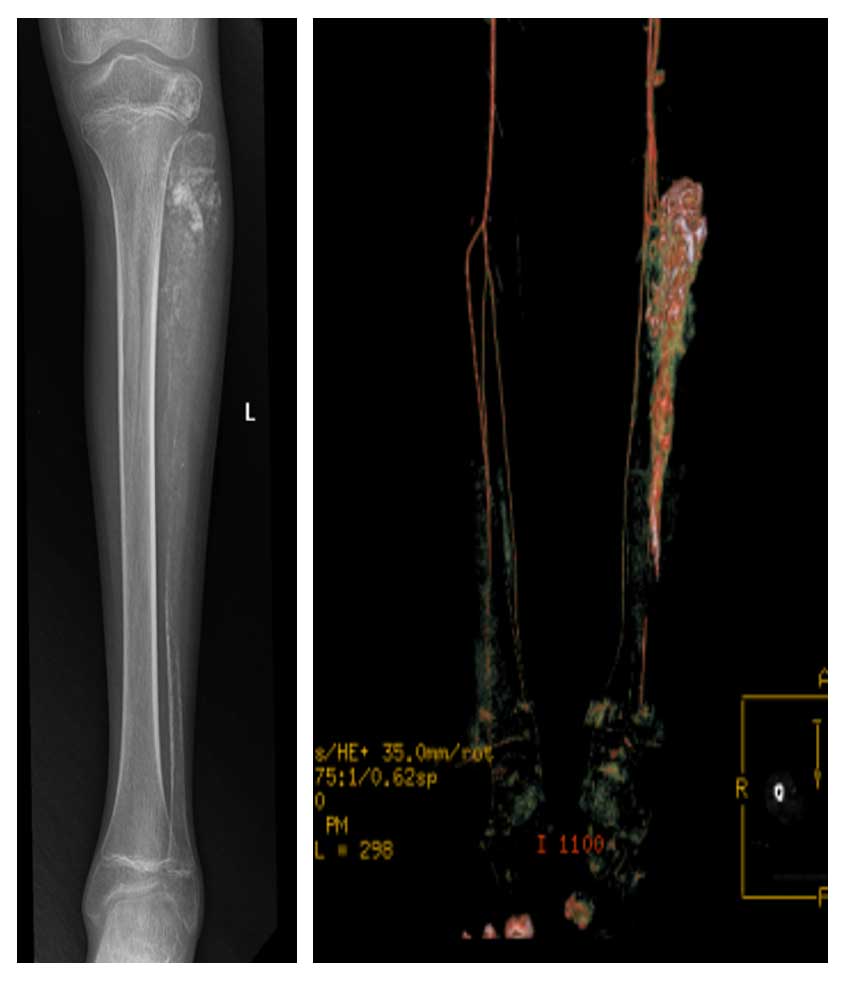

Ameliyat Öncesi: Röntgende fibulanın tamamına yakınında yıkıma neden olan, BT anjiografide yoğun damarlanmanın eşlik ettiği kitle.